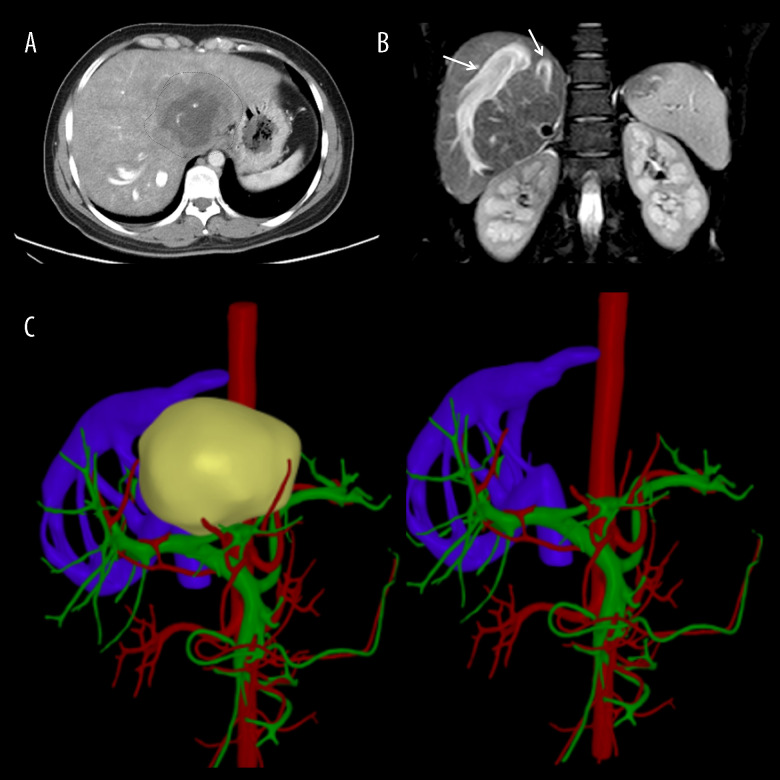

BACKGROUND Alveolar echinococcosis, a lethal parasitic disease, can invade important vessels in the liver. A liver vascular anomaly causes compensatory changes in other blood vessels connected to it because of the close relationship between them. Obstruction of the retrohepatic inferior vena cava and the second hilum can form the intrahepatic venous network and the vertebral venous plexus pathway, which can be demonstrated by hepatic venography and anatomical and autopsy studies. CASE REPORT A Tibetan woman, age 31, with hepatic alveolar echinococcosis and unique intrahepatic hemodynamic features, was referred to our center and underwent successful ex vivo liver resection and autotransplantation. We report our experience and review the literature. In this clinical case, we performed an ex vivo liver resection and autotransplantation without hepatic inferior vena cava reconstruction. After surgery, the circulatory system hemodynamic remained stable, and blood flow in the liver and trunk was unhindered. The patient underwent an uneventful hospitalization and recovery. CONCLUSIONS This clinical case demonstrates the unique venous access, hemodynamic alterations, and surgical decision-making that follow the invasion of significant hepatic vessels by alveolar echinococcosis lesions. HAE exhibits unique collateral vessels, which are uncommon in other diseases. Additionally, this kind of therapy offers fresh perspectives for the surgical treatment of end-stage HAE.